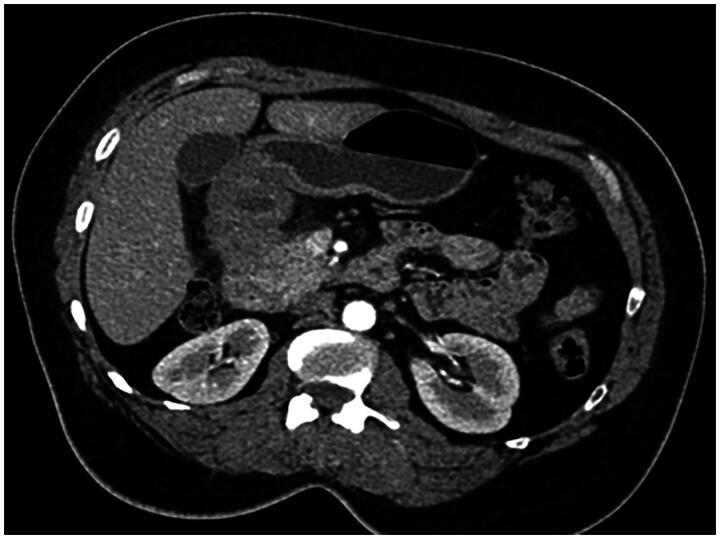

Duodenal bulb adenocarcinoma is a rare malignancy of the gastrointestinal tract. This cancer often presents with an insidious onset, making it challenging to diagnose early. A noteworthy case-study involved a 56 year-old-woman complaining from epigastric transfixing pain, jaundice, and overall health decline. The initial diagnosis suspected was a pancreatic tumor. An abdominal CT scan however showed no abnormality in the pancreas but revealed on the other hand an irregular, non-stenosing, heterogeneous fibrous thickening of the lower aspect of the duodenal bulb. An EGD showed a congested infiltrated area in the post-bulbar region, and Pathological exam confirmed the diagnosis of a primary adenocarcinoma of the duodenal bulb. The purpose of this article is to present the case of a primary adenocarcinoma of duodenal bulb mimicking a pancreatic tumor: a rare presentation of a rare tumor itself and to present points differentiating these two neoplasms. Diagnosis relies on a comprehensive assessment involving clinical, radiological, endoscopic, and histologic features. Integration of advanced imaging modalities, such as CT/MRI, coupled with upper gastrointestinal endoscopy, is crucial for accurate evaluation.